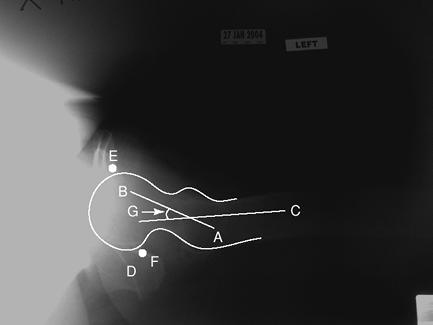

Figure 2-1 Anterior-posterior (AP) view of the pelvis. A, ilium; B, ischium; C, sacrum; D, acetabulum; E, femoral head; F, greater trochanter; G, pubic symphysis.

is performed with the patient supine on the x-ray table. The legs are

internally rotated 15 degrees to compensate for normal femoral

anteversion. The beam should be directed centrally to view the entire

pelvis. This view allows for imaging of the iliac bones, sacrum, pubis,

ischium, femoral heads, and acetabulum and the proximal aspect of the

femur including the greater and lesser trochanter.